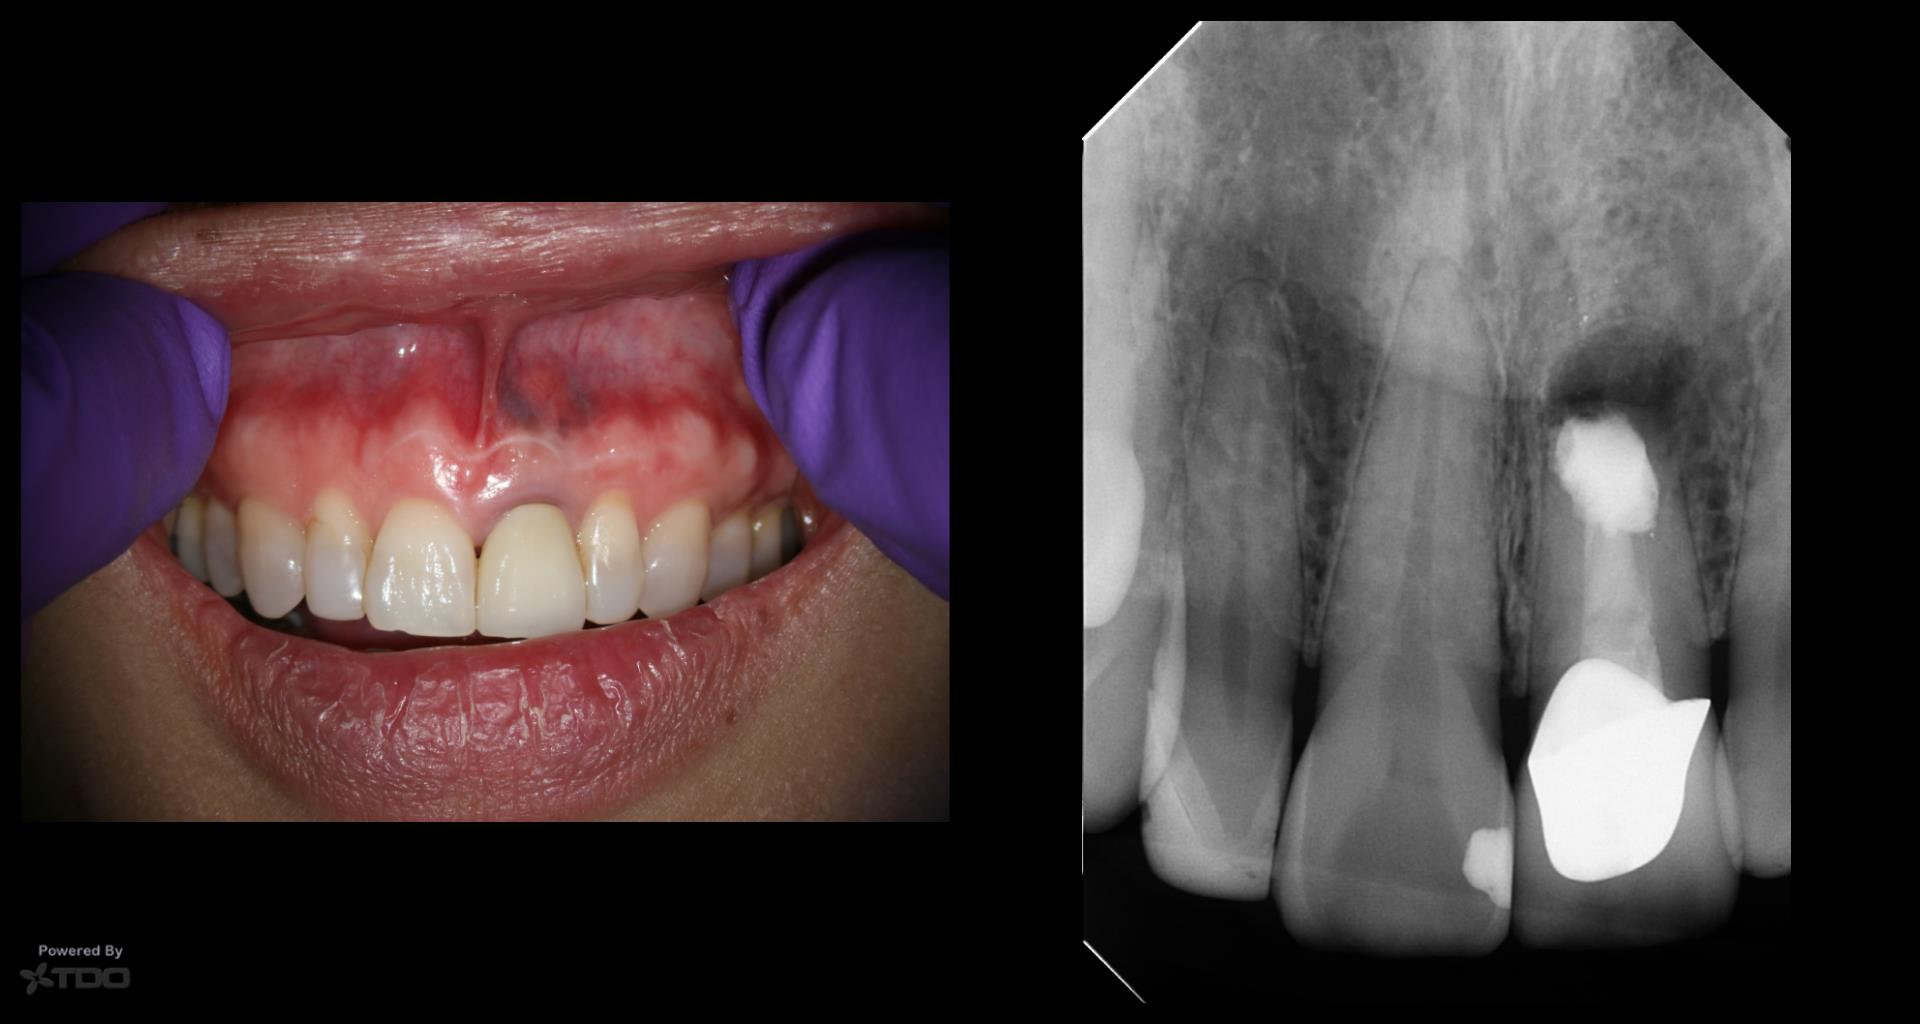

This was interesting because a root frac ture was seen where the prior apico was done. The MTAS was removed and Brassler putty used in this case. Will take a 1 yr CBCT and we will know more. Don’t usually get so much scar formation–so this was surprising…..